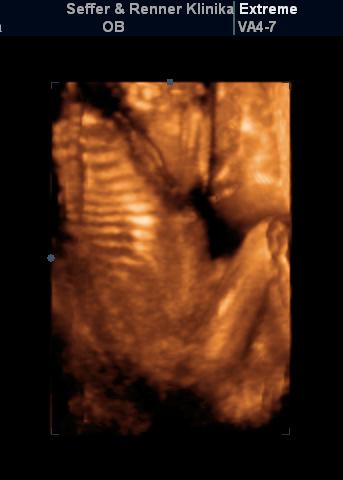

Timi: nagyon mocorgi Bíborka és a legédesebb, mikor nevetett. Tényleg csodás élmény lehet megélni, hogy már az anyaméhben látod a saját kis porontyodat... Annyira várom már, hogy mi is mehessünk.